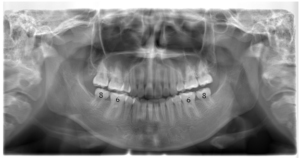

(治療前:写真左)

他院にて矯正治療中での転院となり、当院初診時より、上顎の2本の歯は抜去済みでした。

抜歯済みの歯の部位に合わせて治療を行うため、下顎は計4本抜歯しましたが、親知らずをかみ合わせに参加させることで、上下の歯の数は変わらない計画となりました。